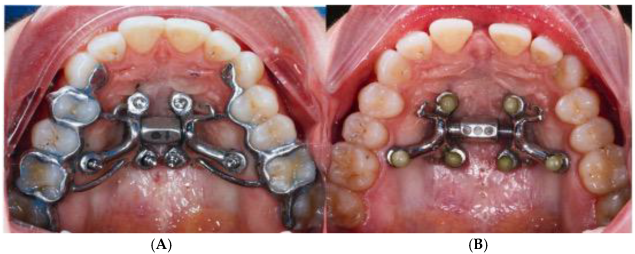

2.1. Description of MARPE Installation Procedure

2.4. Case A: Blind Midpalatal Piezocorticotomy with MARPE Expansion

2.5. Case B: Guide-Assisted Midpalatal Piezocorticotomy